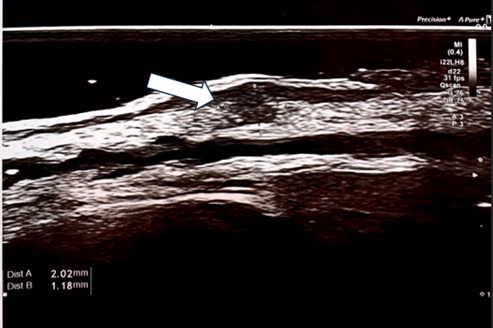

On days 5 and 7 following the procedure, the patients reported the persistence of micro papules in the periorbital areas. The papules were firm, non-painful, with minimal or no visible inflammatory reaction in the surrounding tissues. The patients A and B underwent follow-up consultations, massage and PRP (platelet-rich plasma) autologous injections were performed (Figure 1) (Figure 4). During consultation the status of the papules was evaluated using physical assessment with visual and palpatory control. The patients A and B underwent ultrasonographic examination on 13th day after collagen injection with a high-resolution 22 MHz Canon probe to determine the depth of the micro papules, which concluded the presence of the papules in subdermal layer. (Figure 2) (Figure 5A, B). The patient A underwent a tissue histology examination and 14th day after collagen injection to assess the nature of the papules, the reaction of the surrounding tissue, and the nature of the inflammation, which concluded that the papules are collagen collection without perifocal inflammation (Figure 3). Follow-up consultation was performed on day 28 after injection which concluded resolution of the symptoms, no visible or palpable papules were observed (Figure 5A & 5B).

Figure 5 Ultrasonography of Patient B of right eyelid skin, performed using a Canon Hockey Stick 22 MHz probe, revealed hypoechoic collagen aggregates closely adhering to the dermal layer.